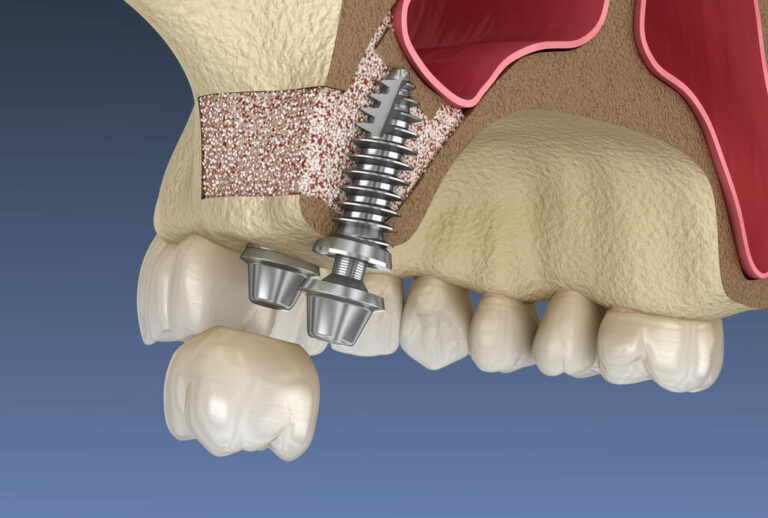

Η ανύψωση ιγμορείου, γνωστή και ως Sinuslift, είναι μια χειρουργική διαδικασία που επιτρέπει την αύξηση του ύψους του οστού στην άνω γνάθο με την τοποθέτηση οστικού μοσχεύματος. Το οστικό μόσχευμα τοποθετείται κάτω από το ιγμόρειο, το οποίο “ανυψώνεται” για να δημιουργηθεί χώρος για τα εμφυτεύματα. Αυτή η διαδικασία είναι απαραίτητη όταν το υπάρχον οστό δεν είναι αρκετό για να υποστηρίξει τα εμφυτεύματα, είτε λόγω απώλειας δοντιών για μεγάλο χρονικό διάστημα είτε λόγω της φυσιολογίας του ασθενούς.

Ανοικτή Τεχνική Ανύψωσης Ιγμορείου (Open Sinus Lift):

- Η ανοικτή τεχνική χρησιμοποιείται όταν το οστικό έλλειμμα είναι μεγαλύτερο και απαιτείται σημαντική ανύψωση του ιγμορείου (άνω των 4 χιλιοστών).

- Κατά τη διάρκεια της διαδικασίας, γίνεται μια τομή στα ούλα για να δημιουργηθεί πρόσβαση στο ιγμόρειο, και η μεμβράνη του ιγμορείου ανυψώνεται με προσοχή.

- Στη συνέχεια, τοποθετείται οστικό μόσχευμα στην περιοχή, το οποίο θα βοηθήσει στην αύξηση του οστικού όγκου. Το μόσχευμα μπορεί να προέρχεται από τον ίδιο τον ασθενή, από δοτές, ή να είναι συνθετικό.

- Ανάλογα με την περίπτωση, η τοποθέτηση των εμφυτευμάτων μπορεί να γίνει είτε ταυτόχρονα με την ανύψωση του ιγμορείου είτε μετά από μερικούς μήνες, όταν το οστό έχει ενσωματωθεί πλήρως.

Στις περιπτώσεις ανοικτής τεχνικής, το οστικό μόσχευμα χρειάζεται 4-9 μήνες για να ενσωματωθεί πλήρως και να είναι έτοιμο για την τοποθέτηση του εμφυτεύματος.